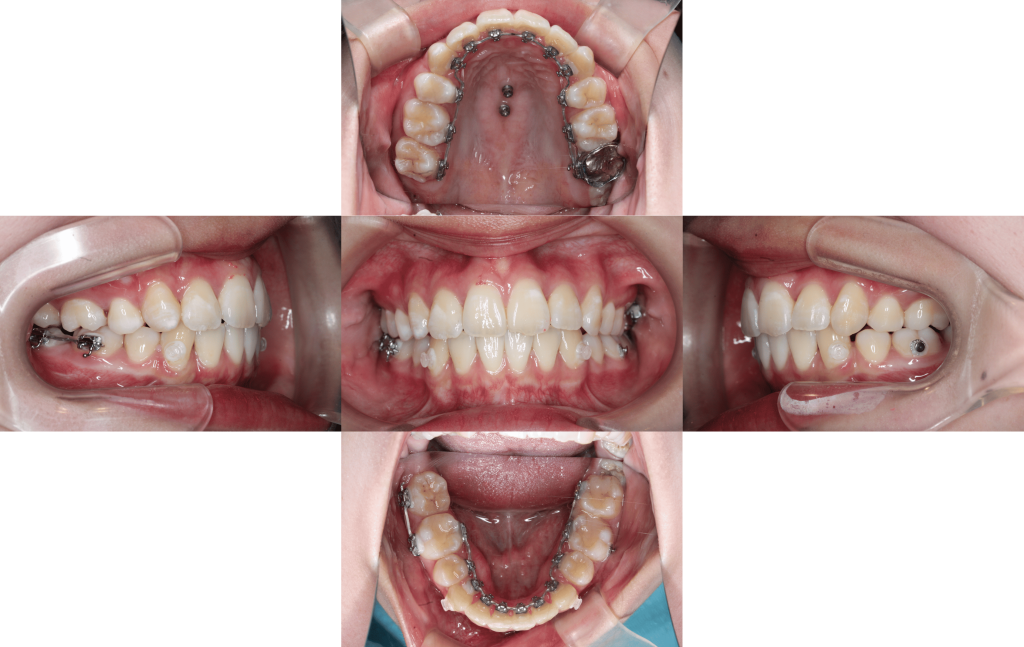

約2年後

約2年6か月後